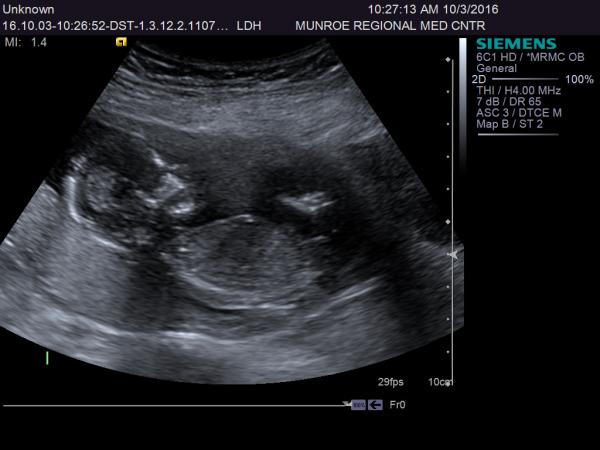

my cousin is 14 weeks 5 days and had an ultrasound today but the tech wouldn't look at gender....so what do you think?Attachment 33252Attachment 33253